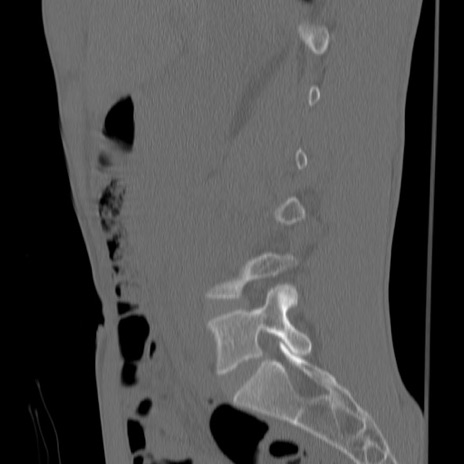

症例3 腰椎CT(矢状断像)

【症例】30歳代男性

【主訴】腰痛

【現病歴】本日旅行先で観光中に、友人と衝突し転倒し受傷。

【身体所見】麻痺なし、右下腿内側前面外側、左下腿内側に知覚鈍麻・しびれ

異常所見と診断は?

腰椎CT